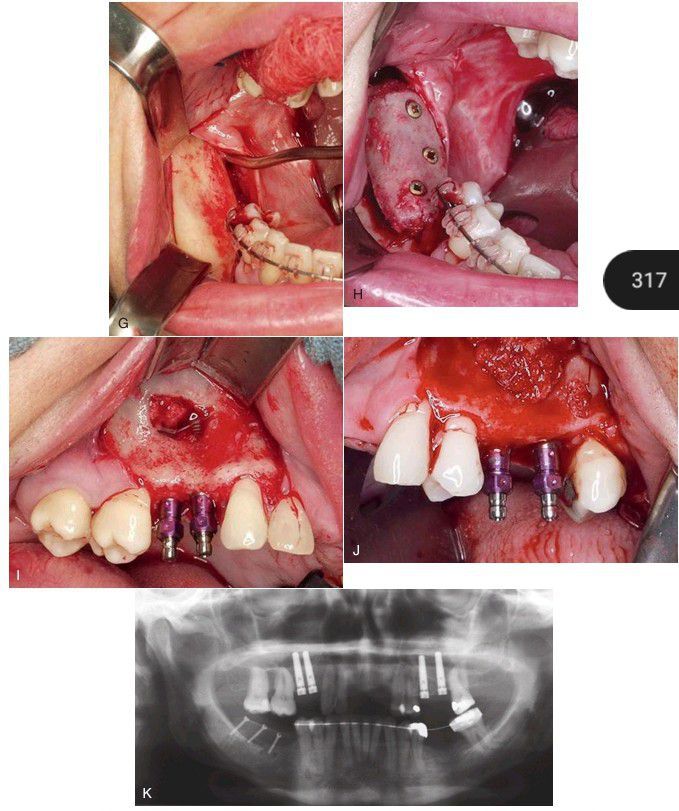

Surgical exposure of atrophic posterior mandible. (H) Fixation of the cortical bone graft. (I) Simultaneous implant placement and sinus lift prior to placement of the bone graft. (J) Completion of the graft placement in the maxillary sinus. (K) Panoramic radiograph after grafting.